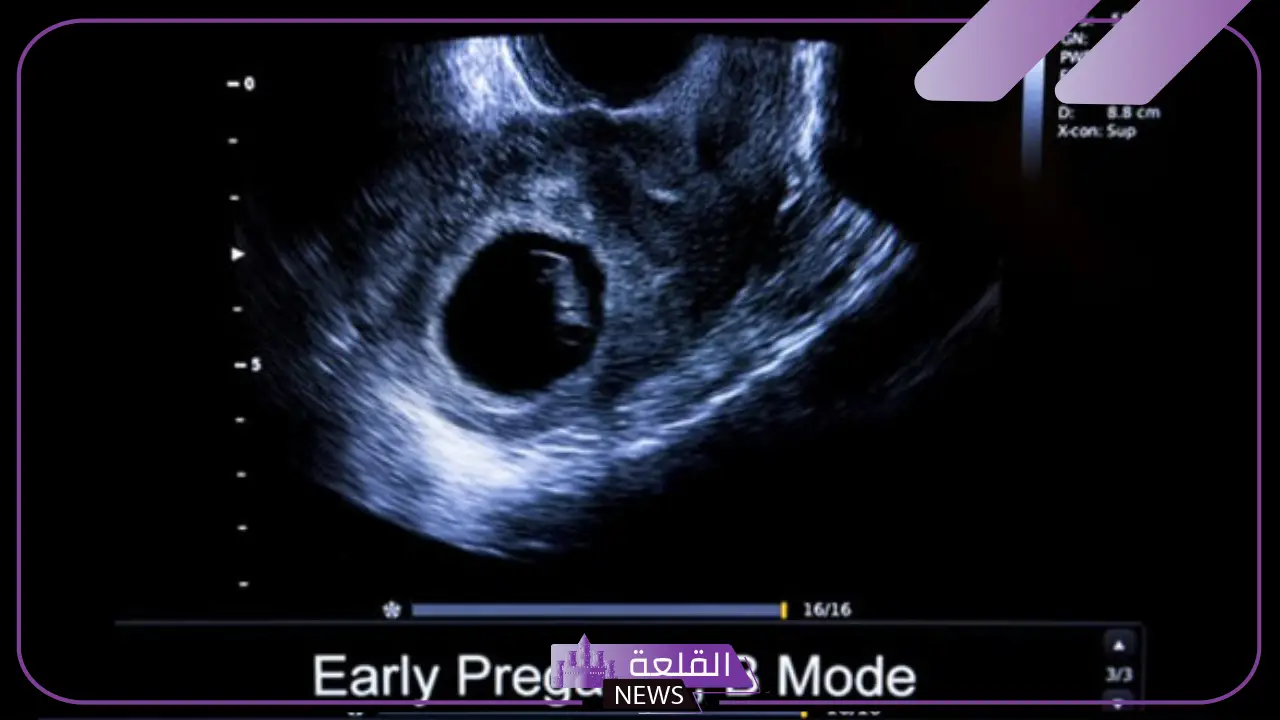

بالنسبة إلى شكل كيس الجنين في الأشهر الأولى من الحمل يكون عبارة عن هيكل بيضاوي أو دائري.

مع مرور الوقت، يتغير شكل كيس الجنين والحجم أيضًا ولكن بشكل تدريجي وهذا بناءًا على نمو الجنين، أما في الشهر الثاني من الحمل يظهر كيس الحمل بشكل أكثر وضوحًا.

في الشهر الثاني من الحمل يكون كيس الحمل قد نما ويمكن رؤيته وسماع نبضات الجنين أيضًا، علاوة على أنه يمكن رؤية كيس الحمل عبر السونار بشكل واضح، ويظهر كيس الحمل إما على شكل دائري أو على شكل بيضاوي ويحتوي على السائل الذي يحيط بالجنين، وفي هذه الفترة يمكن للطبيب بكل سهولة أن يقوم بعملية فحص لكيس الحمل وأبعاد الجنين.